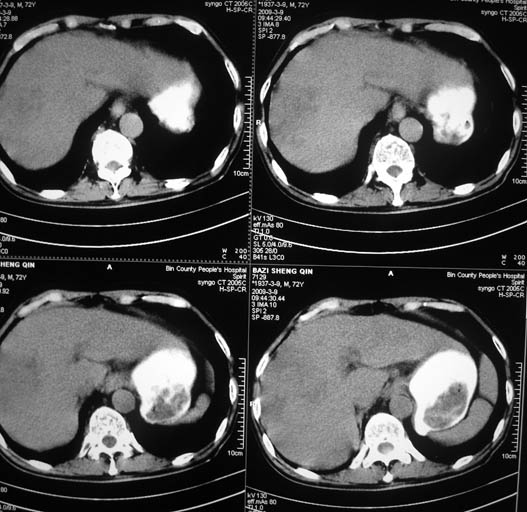

以下是引用ct诊断高手在2009-3-9 21:44:00的发言:[br]增强观看肝内强化及小网膜淋巴结。排除血管瘤肝脓肿

以下是引用影象小泰斗在2009-3-9 22:06:00的发言:[br]肝脏多发占位,不好说是原发肝癌或肝转移瘤!建议强化!

以下是引用黑白光影在2009-3-9 22:19:00的发言:[br]肝脏多发性占位性病变,腹膜后多发淋巴结肿大,建议行ct增强扫描检查。

以下是引用随光逐影在2009-3-9 22:15:00的发言:[br]1)肝脏多发性占位性病变(肝癌?肝转移瘤?);建议行ct增强扫描检查。2)腹膜后多发淋巴结肿大。